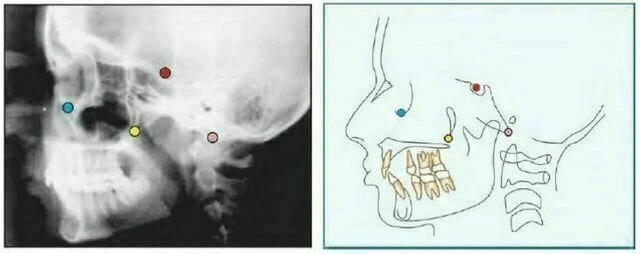

Condylion (Co) là điểm sau nhất và trên nhất ở lồi cầu xương hàm dưới.

Articulare (Ar) Giao điểm của mặt dưới nền sọ và mặt sau của cổ lồi cầu xương hàm dưới. Articulare được sử dụng một cách có hệ thống cùng với Condylion khi điểm này không nhìn thấy rõ. Sự thay đổi của vị trí lồi cầu sẽ làm điểm Artculare dịch chuyển.

Pterygomaxillary Fissure (Ptm) Có một hình ảnh có hình giọt nước, bóng phía trước là mặt sau của lồi cùng xương hàm trên. Điểm Ptm là giao của biên giới phía dưới của lỗ tròn với thành sau của khe chân bướm hàm.